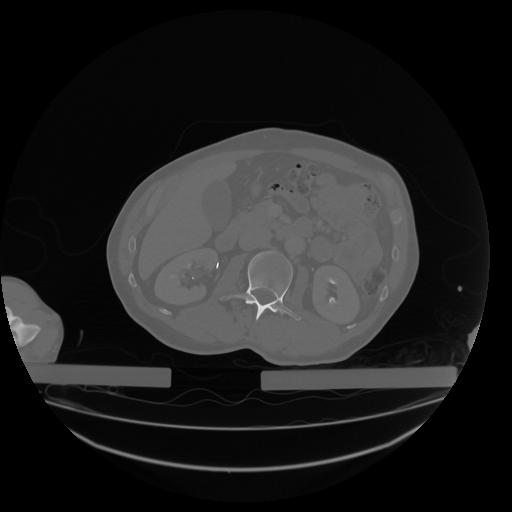

34 CUERPO,CE,Vol,1.0,CUERPO,,